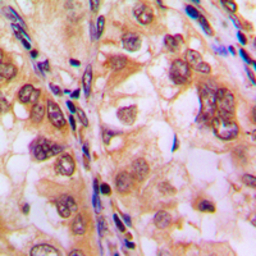

IHC-P analysis of formalin fixed human lung cancer tissue section using GTX32364 HDAC8 (phospho Ser39) antibody.

Antigen retrieval : Heat mediated antigen retrieval with sodium citrate buffer (pH 6.0)